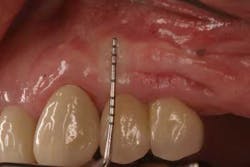

Fig. 3a: Edentulous Nos. 12 and 13 slated for implant therapy with a limited amount of keratinized tissue.

Fig. 3b: Soft tissue Mucograft placed at the time of implant surgery in order to augment keratinized tissue height and thickness. Primary closure was not obtained over this graft.